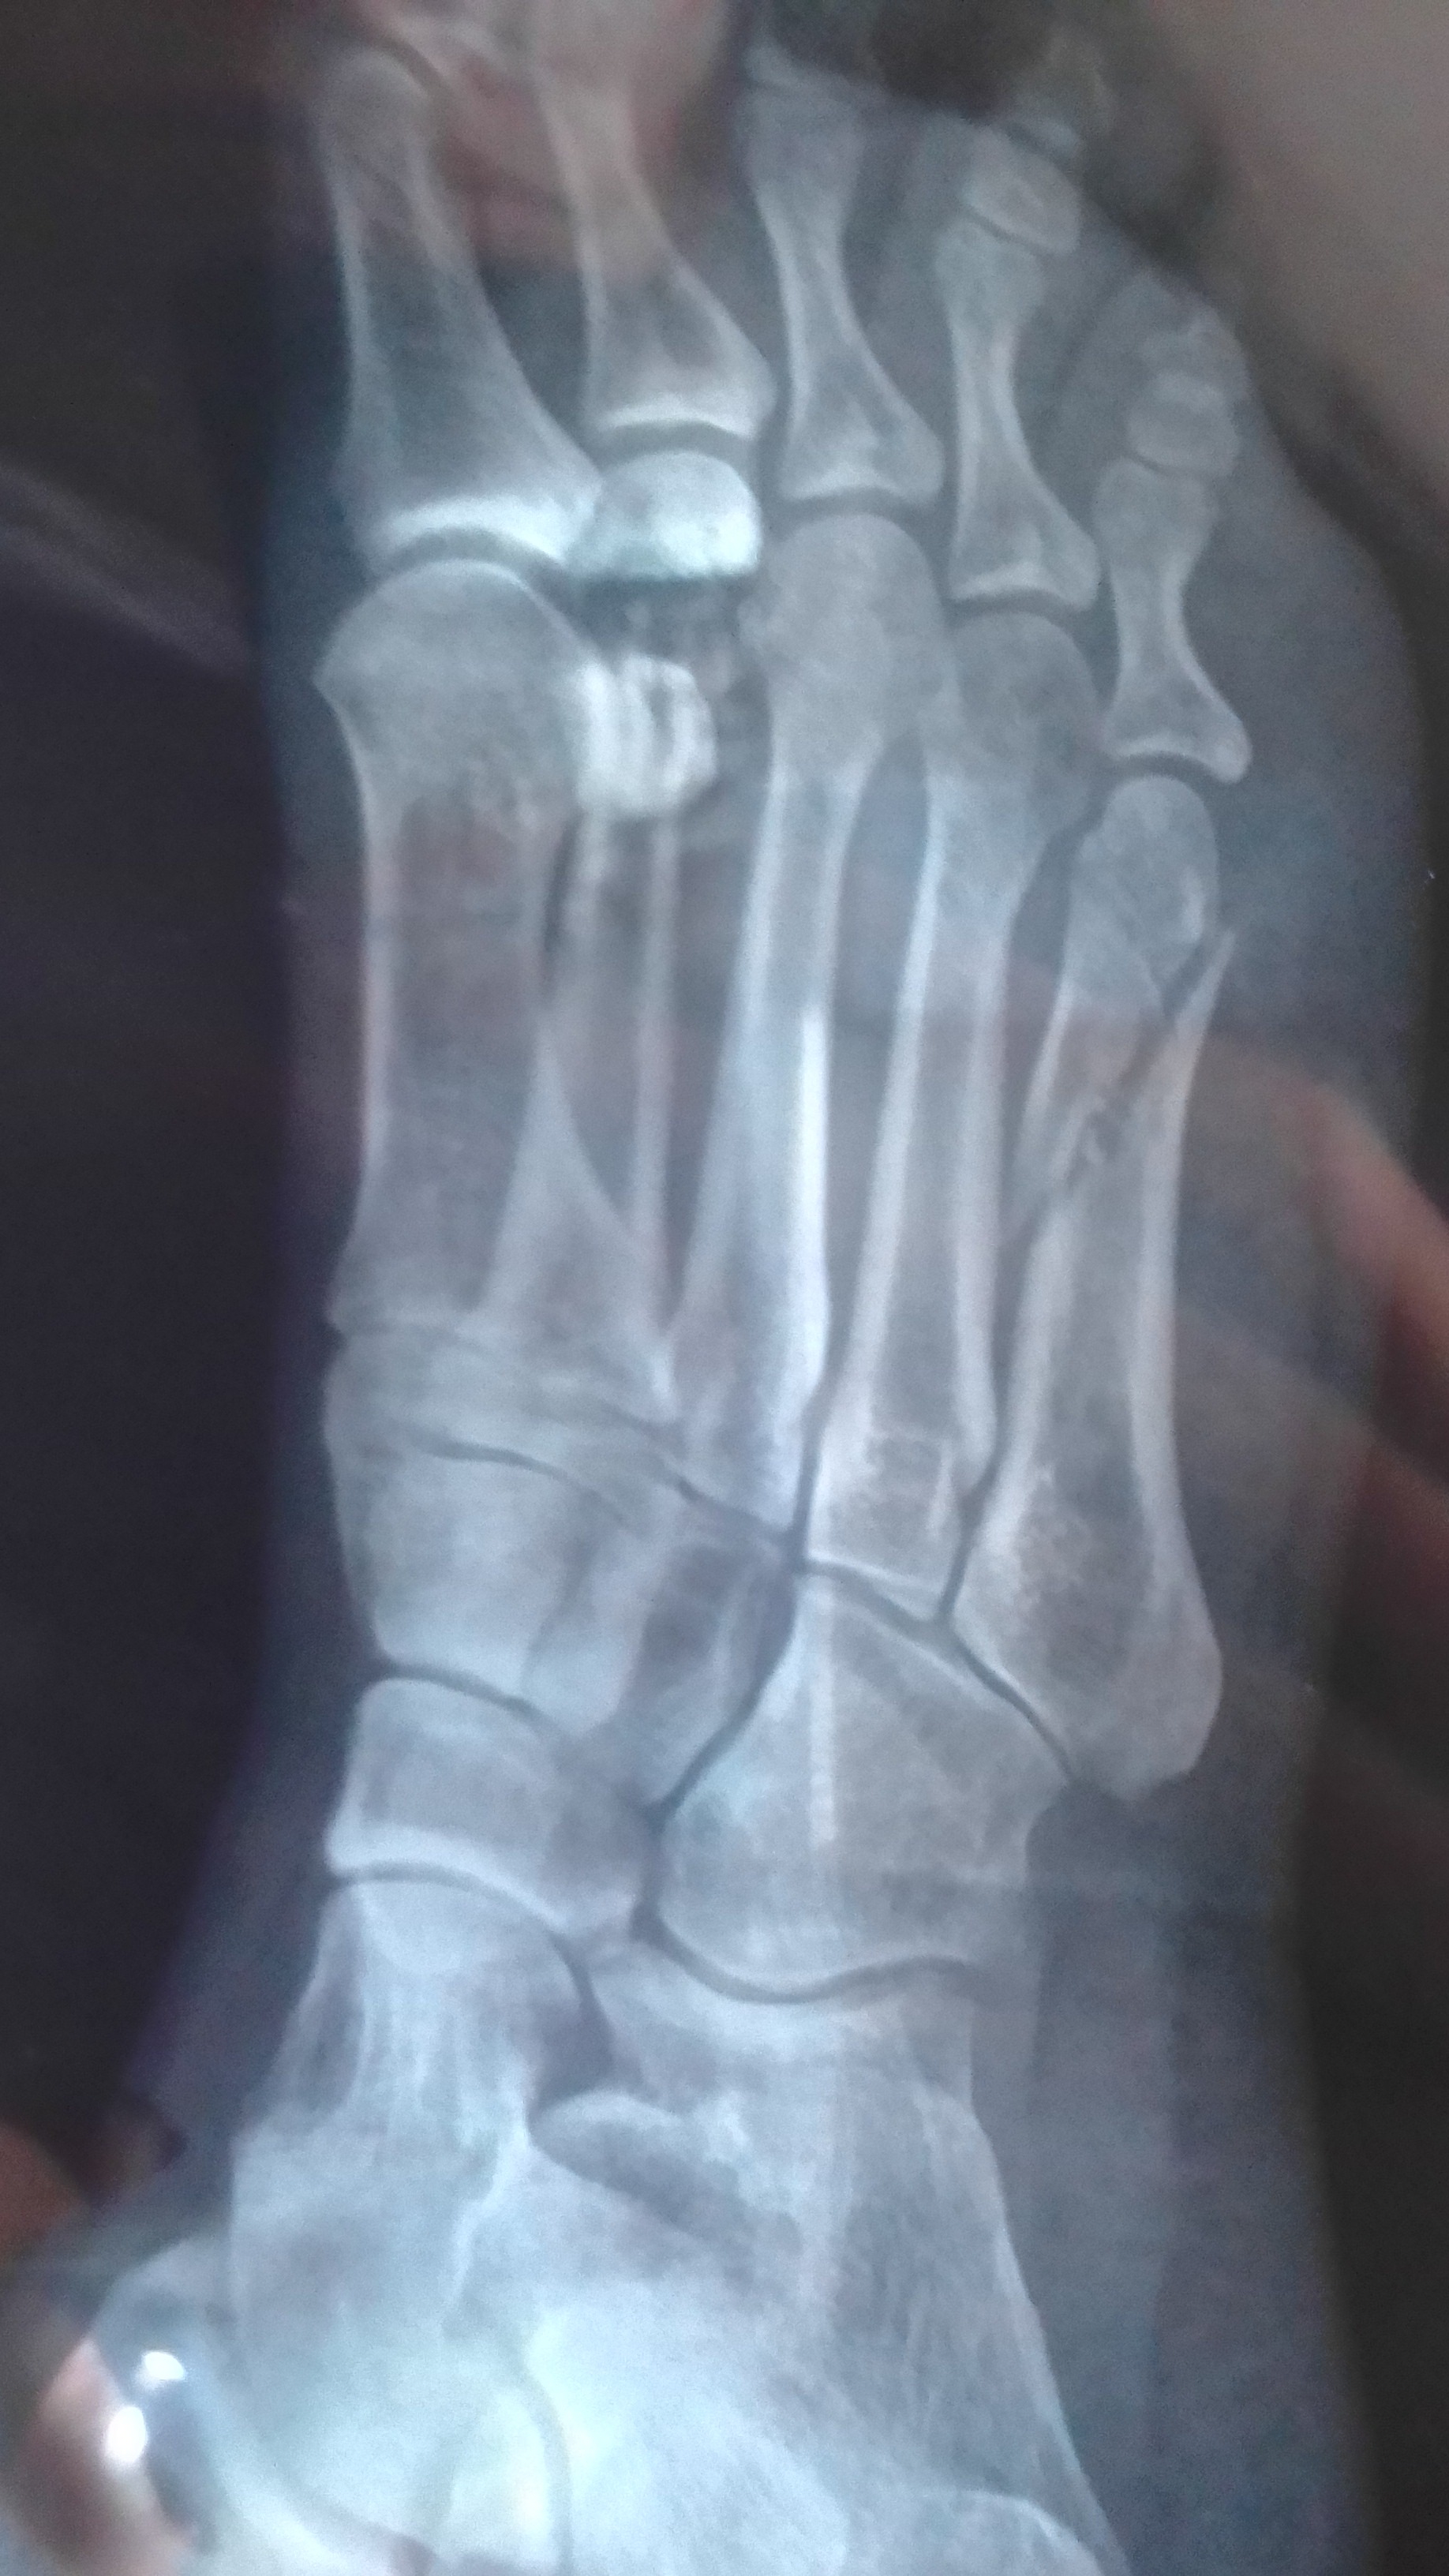

Ayúdame a caminar de nuevo: fractura de pie y recuperación

Hola, mi nombre es Shelly y hoy estoy aquí para pedirte un poco de apoyo en un momento muy difícil para mí. Hace poco sufrí una fractura en el pie que ha cambiado por completo mi rutina y mi vida cotidiana. La lesión fue dolorosa y, lamentablemente, ha requerido atención médica urgente, estudios, medicamentos, y ahora, una larga recuperación que me obliga a guardar reposo absoluto.